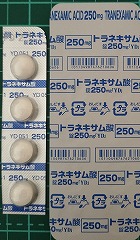

2021.11.13より 西原クリニック 0968-62-0622

22.10.29 鼻炎薬吸引 モメタゾン点鼻液50μg 噴霧用 5mg10g 杏林 56噴霧用